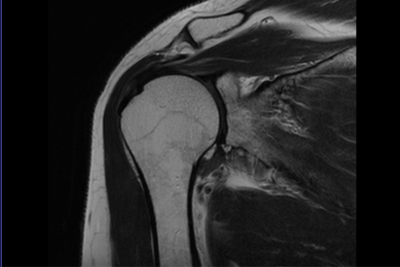

МРТ плечевого сустава

МРТ плечевого сустава — современный диагностический метод, который дает возможность получить точное трехмерное изображение мягких и костных тканей плечевого пояса. При проведении магнитно-резонансной томографии удается исследовать на патологические отклонения суставов, сосудов, костей, мышц и других тканей плеча.